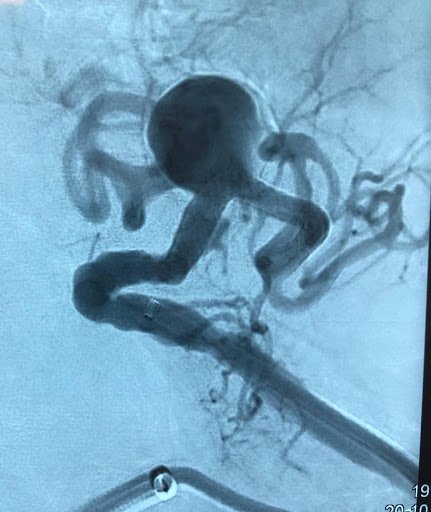

Aneurismas arteriales

Tratamiento quirúrgico y endovascular de aneurismas aórticos y viscerales con planificación individualizada basada en anatomía, riesgo clínico y evidencia científica.

• Aneurismas arteriales Tratamiento quirúrgico y endovascular de aneurismas aórticos y viscerales con planificación individualizada basada en anatomía, riesgo clínico y evidencia científica.